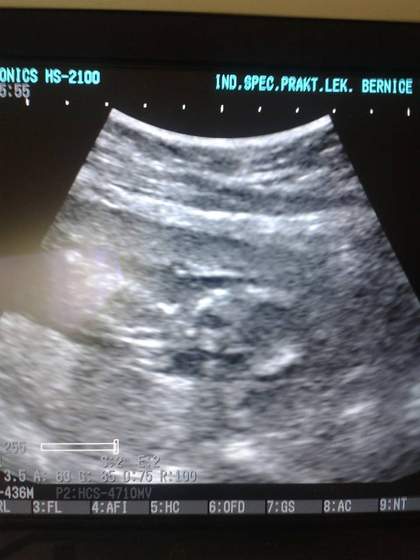

Nasze wizyty: terminy, zdjęcia USG, wyniki

Annte ja również gratuluję parki! Wiesz, ja myślę, że jakby było coś nie tak, to by lekarz powiedział. Ja wiem, to nie jest super argument, ale szkoda się denerwować. Następnym razem zapytaj wprost może o wagę itp? U nas nie podają takich szczegółów i bardzo nad tym ubolewam, więc mam niedosyt po każdym usg. Ale ja wyjścia nie mam, bo nawet jak zapytam to usłyszę, że to są pomiary tylko orientacyjne dla nich :-( Ty jak masz okazję,to śmiało....22 tc to wciąż dobry czas na usg polowkowe. Kurcze, nie smutaj się. Zobaczysz, że następnym razem będzie lepiej :-)

Annte - gratuluję parki ale super, pewnie dziewczyny maja racje że gdyby było coś nie tak to lekarz kazał by Ci szybciej przyjść, jednak ja tez czułabym niezadowolenie szczególnie jeśli w poprzedniej ciąży zachowywał się inaczej, tez mnie zawsze ciekawi ile mierzy i waży maluch, a co do połówkowego to może zrobi Ci je po prostu na wiiztycie za te cztery tygodnie. Ja będę mieć połówkowe bardzo późno dopiero 11 sierpnia u mnie to będzie wtedy 22 i 3 dni ciąży

ANNTE gratulacje parki, to chyba taki idealny traf ;-) Co do lekarza. No faktycznie taki mało sympatyczny. Może dla własnego spokoju pomyśl o innym? Może akurat taki jego dzień, chociaż mnie ostatnie USG róbil lekarz małowygadany. Poza długością nic nie powiedział. Dopiero o przeziernosci powiedział, jak zapytałam!

Ja wizytę miałam wczoraj. USG nawet się nie spodziewałam, bo lekarz nie ma sprzętu nawet. Oczywiście badanie podwozia, łącznie z badaniem PH, bo marudzilam o gęstym śluzie. Przegląd badań, no i hemoglobina znów w dół poszła, mam jeść "żelazowo".

Myślałam, że zleci mi połówkowe kolo 20 tygodnia, czyli za tydzieńub dwa, a on kazał zrobić w tygodniu poprzedzającym wizytę na 29 lipca.... Jajo zniosę! Kwadratowe!!!!

Kochane bylam dziś na wizycie niestety nie robiła mi usg :) za 3 tyg mam prenatalne :) wiec mowila ze dzidzius bedzie wiekszy i bedziemy mogli okreslic płeć :)i odrazu wszystko pomierzy :) dostalam witaminy bo zaczely mi wypadać włosy :) a tak to wszystko jest w porządku :) jeszcze nie czuje ruchów chyba :)